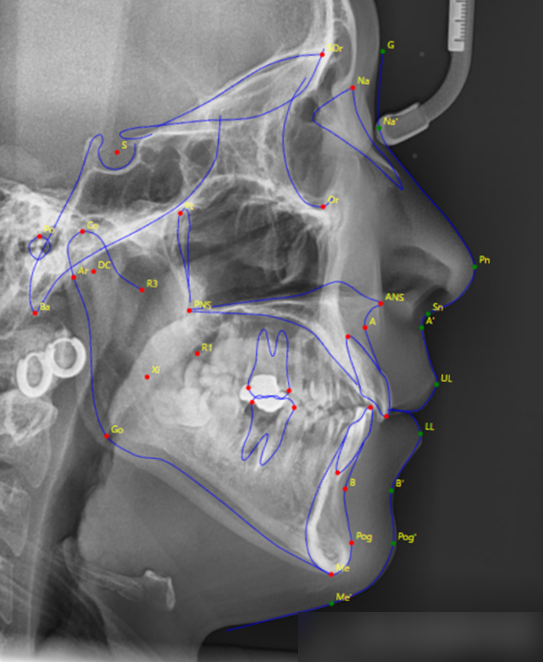

측면에서는 얼굴이 수직적으로 길며

아래턱이 작고 뒤로 들어간 형태,

즉 골격성 2급 부정교합에

해당하는 양상이 관찰되었습니다.

촬영일 : 23.12.04